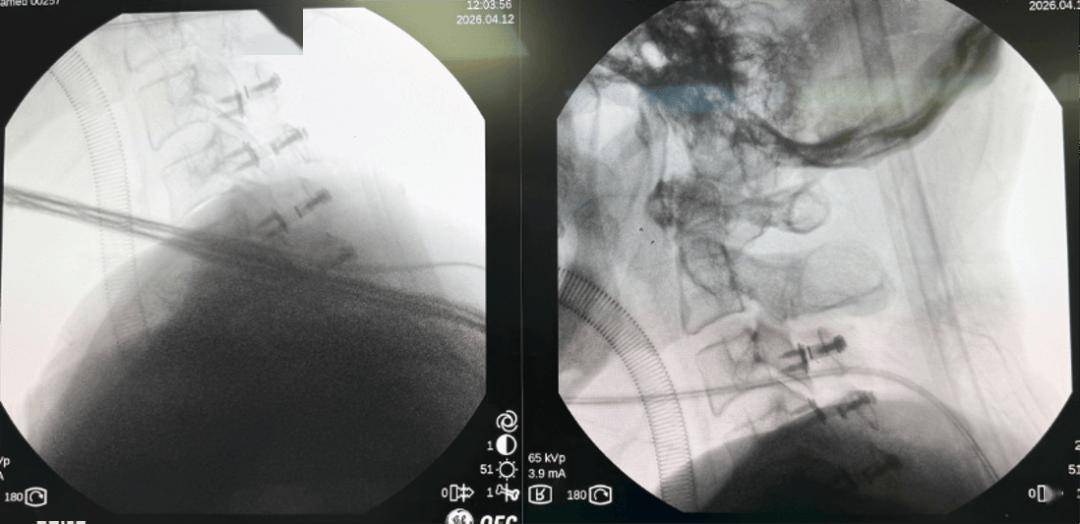

患者术前核磁共振影像

术中,骨病中心三部主任医师许崧杰团队紧抓神经修复“黄金窗口期”,与麻醉手术中心团队密切配合,实施颈椎后路单开门手术,彻底解除血肿对颈髓的压迫。

术后患者四肢肌力即出现恢复迹象,成功避免终身截瘫,为后续康复奠定基础,体现了中心对复杂病例的同质化高水平救治能力。

患者术后X线影像